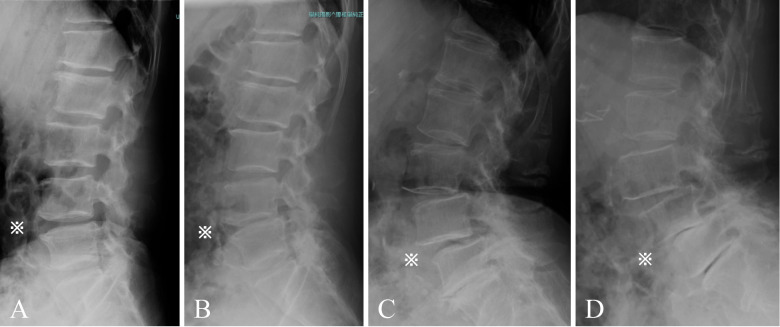

Methods: We reviewed the data of patients with >5 years of postoperative follow up. Radiographic PSD was defined as either the development of an anterolisthesis or retrolisthesis of >3 mm or a decrease in disc height of >3 mm during the 5-year follow up. On the basis of intervertebral segments, the association between PSD and other preoperative clinical findings was analyzed.

Results: Overall, 840 lumbar segments (L1-L2 to L5-S1) in 168 patients, with a mean age of 69.5±9.2 years, met the inclusion criteria. PSD was observed in 162 (19.3%) lumbar segments. A logistic regression model identified that Cobb angle ≥10° (OR 2.53, 95% CI 1.50-4.24), spondylolisthesis ≥3 mm (OR 4.447, 95% CI 2.06-9.58), and level of segments were more likely to have PSD at the non-decompression level; additionally, lateral listhesis ≥3 mm (OR 2.91, 95% CI 1.08-7.81) was more likely to have PSD in the decompression segments. In clinical outcomes in patients with PSD at baseline and the 5-year follow-up, no significant difference was found.

Conclusions: Even though PSD does not correlate with worsening symptoms, our study confirms that a higher degree of pre-existing disc degeneration is indicative of a higher PSD in 5 years.